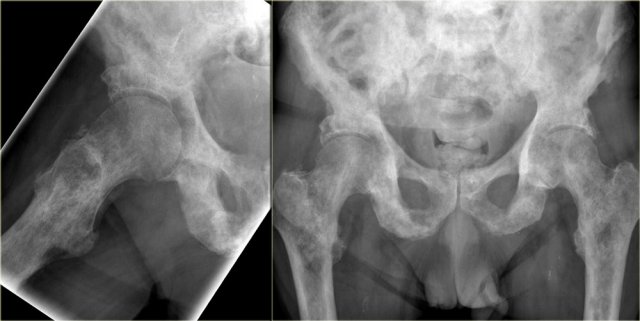

Here a patient with both sclerotic and osteolytic metastases.

It is a male patient, so your first thought is prostate cancer, which this patient had.